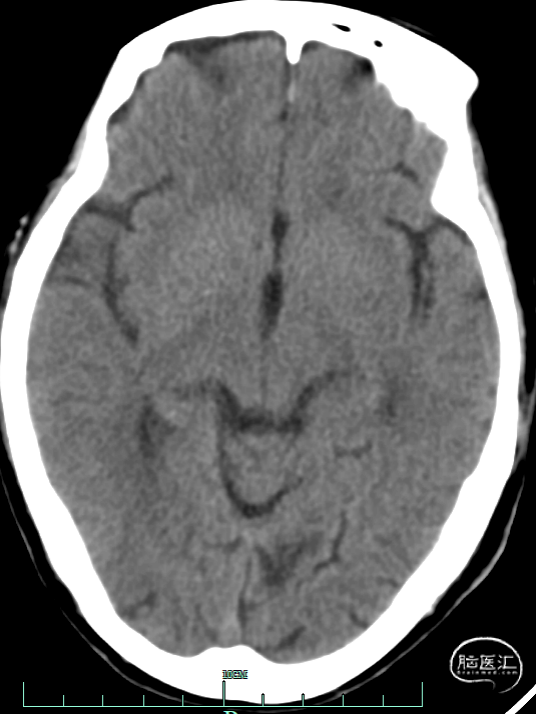

术前影像资料